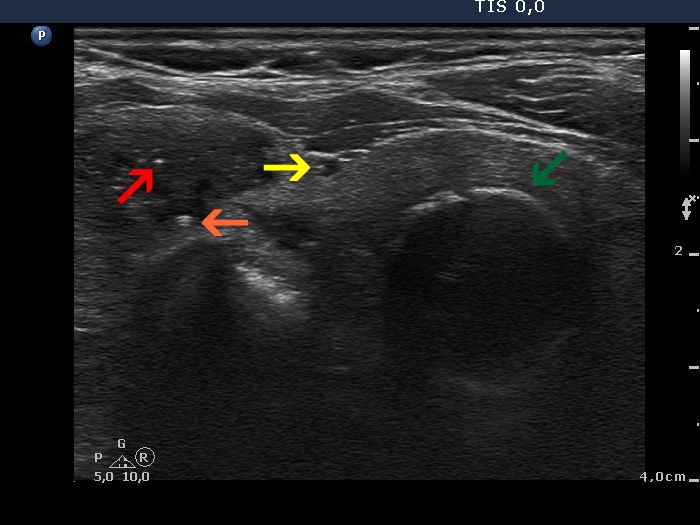

Study on 100 consecutive patients with thyroid nodule - case 037 (ultrasonographic picture 12)

Left lobe, transverse scan. Four types of intranodular hyperechogenic figures are demonstrated in this image. The bright microcalcification is marked with red arrow, non-specific granulation is marked with yellow, the coarse calcification is pointed with green arrow, while the comet-tail artifact does with an orange arrow.